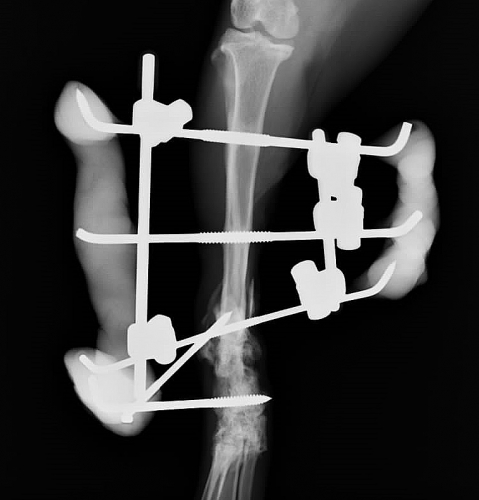

1か月後、最終的なレントゲン検査を行い、すべての固定を除去いたしました。

左下の写真がすべての固定が除去された後の骨折部位の写真です。赤矢印で示した骨のふくらみが、仮骨といわれるもので、骨折部位を横から支えています。これは長期間かかりますが、元の骨に吸収されて収斂していきます。